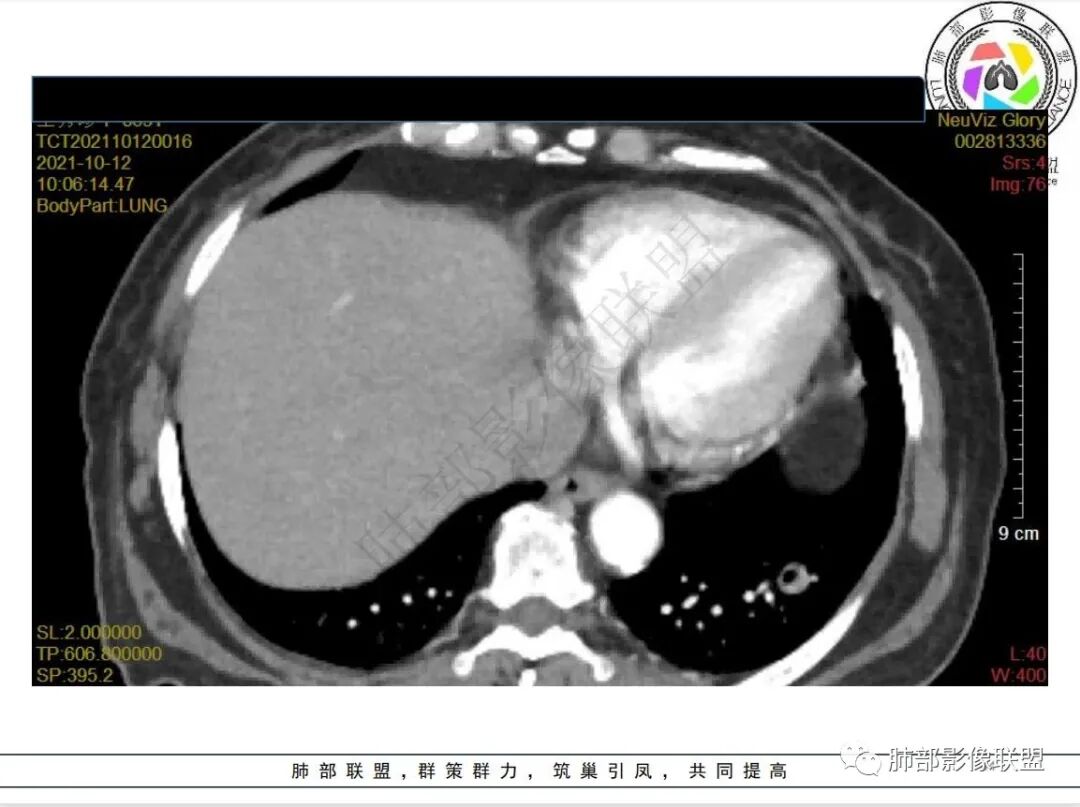

4.白血病化疗后,CT上出现多发结节,边缘可见晕征,病灶内可见多发坏死,右肺中叶肺动脉可见充盈缺损,右肺中叶可见融冰征,右肺中叶肺动脉侵犯栓塞伴右肺中叶肺梗死,可符合真菌感染。

血管侵袭性曲霉病是最常见的类型,其特征是真菌菌丝侵入和阻塞中小肺动脉,形成凝固性坏死、肺泡出血或出血性梗死。

6.肺曲霉病典型的CT表现是结节周围有磨玻璃样的晕征表现,或胸膜为宽基底的楔形实变。晕征表现为曲菌感染的肺结节伴梗死和凝固性坏死,周围有肺泡出血。最终可出现空泡征象,并可观察到中央坏死组织与周围肺实质分离形成空气新月征。